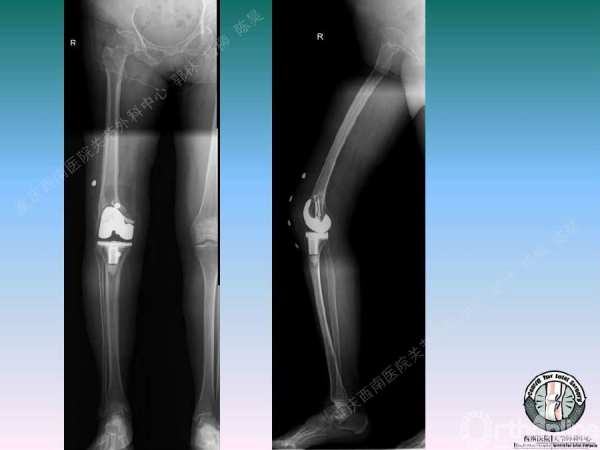

导读:文中,来自重庆西南医院的郭林教授为大家介绍了股骨冠状位关节外畸形的TKA的相关知识,并详细阐述了关节外畸形的概念、诊断、关节内滑移截骨技术等相关内容。

滑移截骨纠正关节外畸形